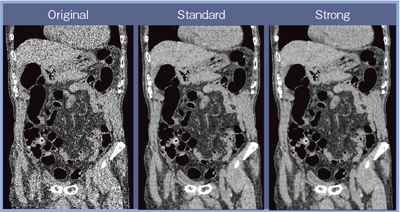

図5に,CTCのオリジナル画像,AIDR 3DのStandard,Strongそれぞれの画像を示す。CTDIvolは1.90mGyと低線量だが,Strongでは大幅なノイズ軽減が実現しており,高精細な画像が得られている。

![]() 図5 AIDR 3Dの有無による画像の比較(CTDIvol:1.9mGy) |